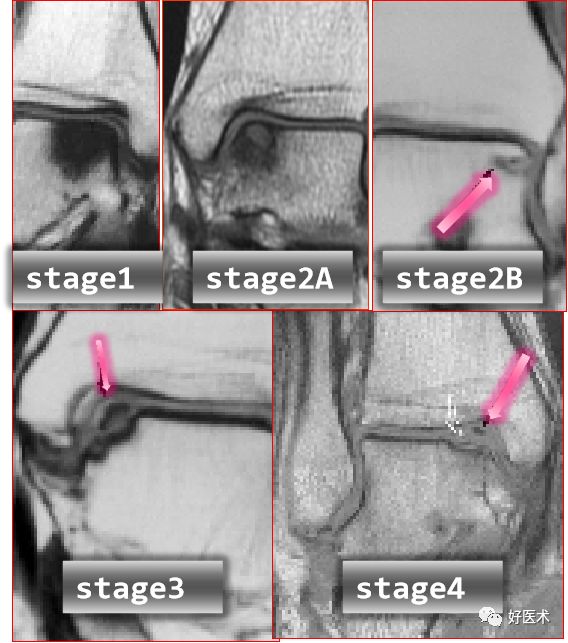

距骨骨软骨损伤分级

1度损伤:

2度损伤

3度损伤